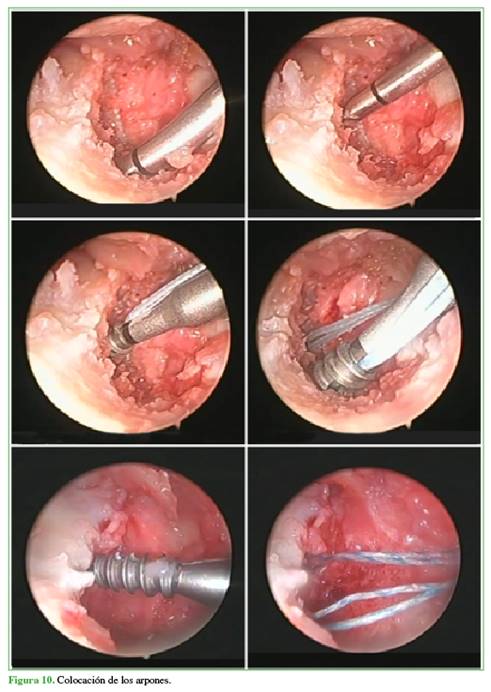

Luego se colocan dos arpones hacia la cavidad sigmoidea. Estos dos arpones se ubican levemente oblicuos a 5 mm aproximadamente la articulación radiocarpiana. Utilizamos arpones con agujas de 2,2 mm de ancho por 8 mm de largo. Se introduce un arpón por el portal 6R y el otro, por el portal 6U para obtener un buen ángulo de colocación (Figura 10, Esquema 5).